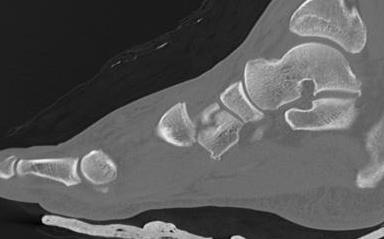

CT scan

Dorsal displacement of metatarsals

Compression fractures / nutcracker of cuboid